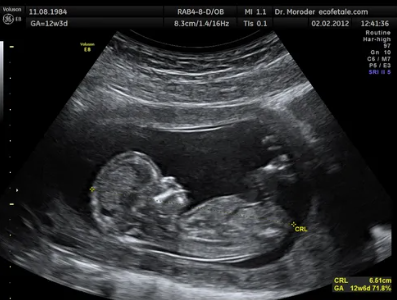

초음파실은 유난히 밝았다. 형광등은 낮처럼 고르고, 기계들은 숨을 쉬지 않는 금속처럼 조용했다. 의사가 말없이 젤 뚜껑을 ‘찍’ 열고, 배에 차가운 것을 펼쳤다. 소독약 냄새가 입천장에 붙었다.

“숨 들이마시고요… 배 힘 빼세요.”

프로브가 슥— 움직일 때마다 화면에 검은 타원이 떴다 사라졌다. 심박선은 없었다. 옆 프린터가 짧게 ‘끽—’ 하고 돌다 멈췄다. 사진은 나오지 않았다.

“임신 사실, 알고 오셨어요?”

“아뇨… 오늘 처음…”

미라의 목소리가 화면 속 어둠에 스며들었다. 의사가 프로브를 잠깐 떼었다. 장갑 낀 손끝에서 젤이 한 방울 또르르 흘렀다. 그는 화면을 본 채로, 아주 조용히 물었다.

“너도…”

다음 음절이 금속성으로 갈렸다.

“…밝히니?”

“네…?” 미라는 순간, 잘못 들은 줄 알았다.

의사가 고개를 천천히 돌렸다. 입꼬리가 실밥 터지듯 양옆으로 늘어났다. 웃음 소리는 없었고, 웃음의 모양만 얼굴에 길게 그어졌다. 형광등은 깜빡이지 않았다. 방은 끝까지 밝았다.

젤이 배에서 식어 내렸다. 기계가 마지막으로 ‘딱’ 하고 눌린 듯한 소리를 냈다. 프로브가 복부를 짓눌렀다. 거기서 한 뼘 더 내려앉자, 속에서 질긴 끈을 당기는 통증이 척추뼈로 번졌다.

프린터가 사진 한 장을 뱉었다. 아무것도 없는 초음파 사진 귀퉁이에 흐릿한 빨간 글씨와 시간이 인쇄되어 있었다. 박미라 11:59

미라는 고개를 들지 못했다. 의사의 웃음은 더 이상 표정이 아니었다. 조롱이었다. 그 무음의 웃음이 방 안을 가득 채우자, 화면 속 타원은 아주 천천히, 완전히 꺼졌다.